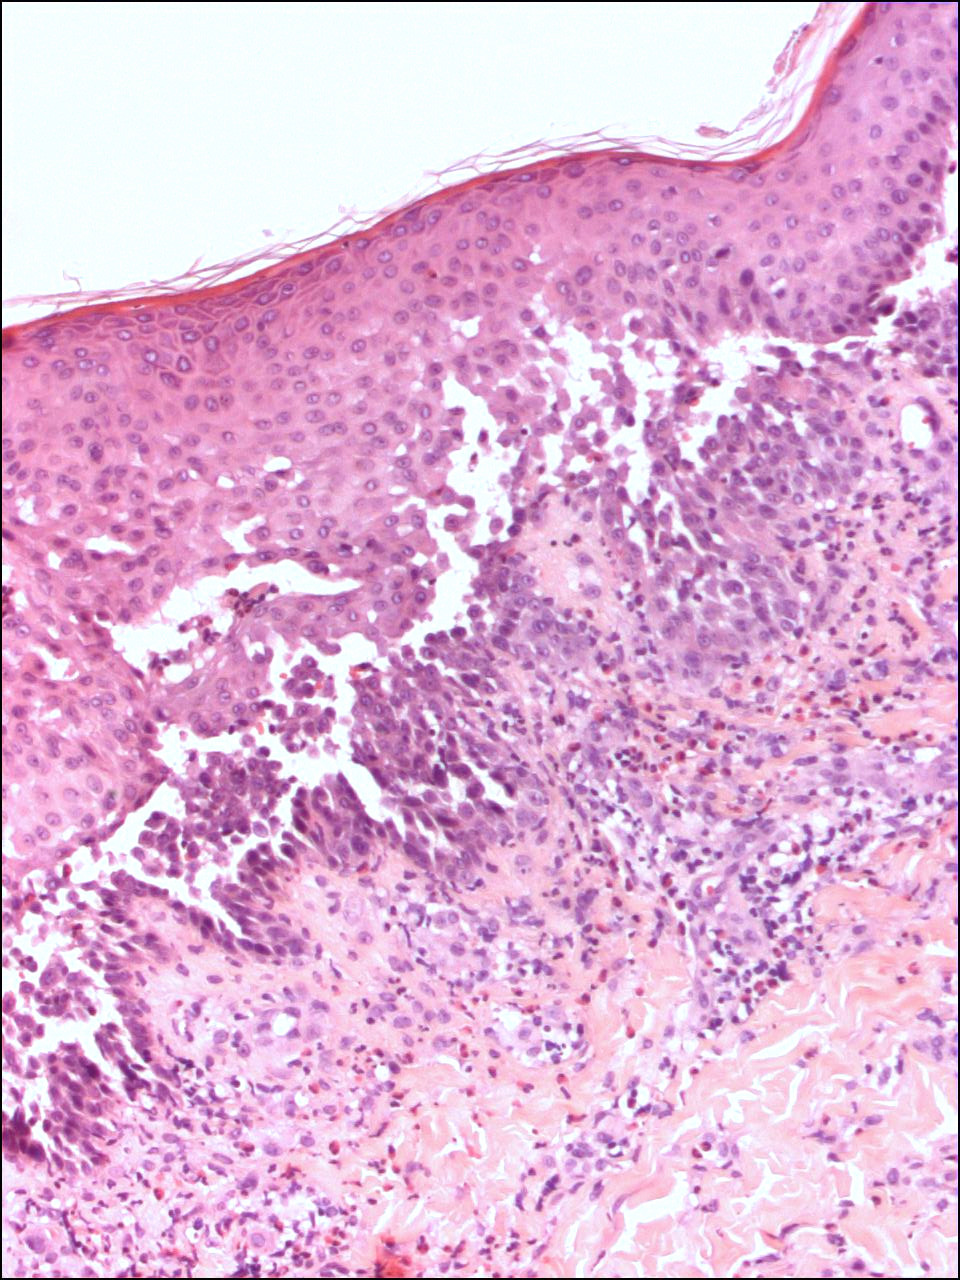

PA:Histologisch

is er sprake van een intra-epidermale splijting (

acantholyse) op suprabasaal

niveau. De keratinocyten liggen op sommige plaatsen volledig los van elkaar

hetgeen de indruk maakt van een bouwvallige ingestorte muur ('dilapidated brick

wall'). Het histologisch beeld is moeilijk te onderscheiden van gewone pemphigus,

maar wel met immunofluorescentie (negatief bij Hailey-Hailey). Bij beide

ziekten is de blaar het gevolg van acantholyse. Verschillen zijn

dat de acantholyse bij Hailey Hailey uitgebreider is en over de hele epidermisdikte voorkomt, en

dat de

dyskeratose minder is

dan bij pemphigus.

| PA pemphigus

benigna |

PA pemphigus